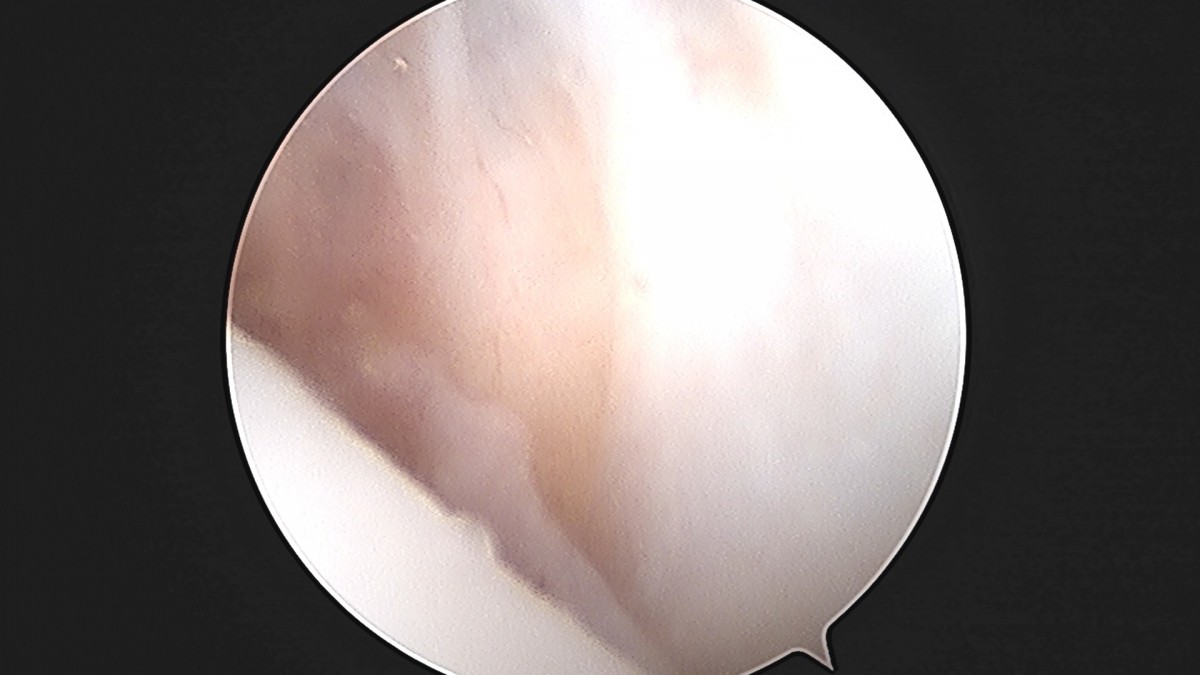

정지영원장님 발목 인대 봉합술 채이O 환자

작성자 최고관리자 댓글 0건 조회 718회 작성일 25-09-16 17:02